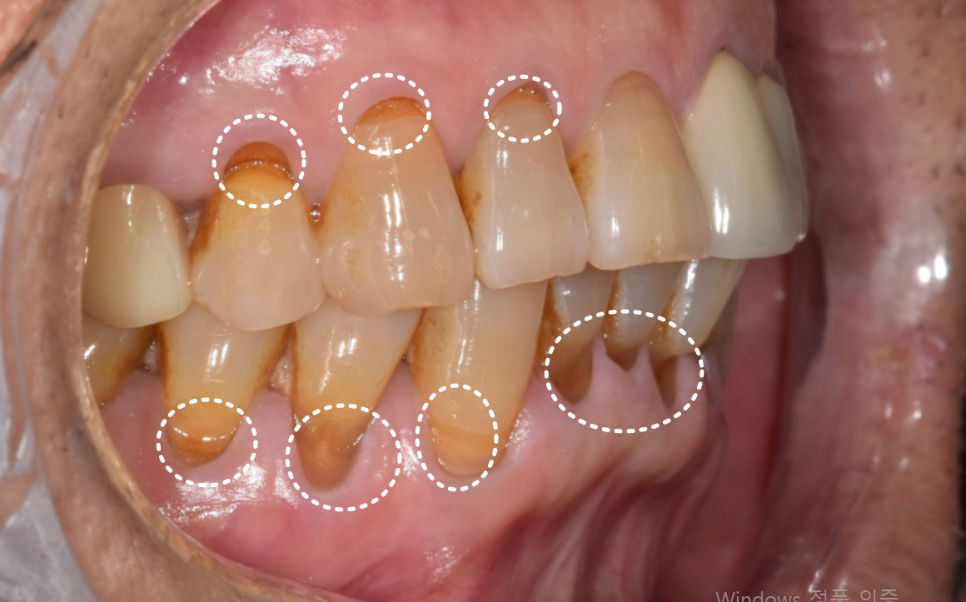

송곳니 쪽만 반대교합으로 인해 잇몸이 내려앉고 치아가 길어 보이는 상태

그로 인해, 유달리 힘을 많이 받는 치아는

더 길어 보일 수 있습니다.

이 환자분이 저희 병원에 오시게 된 이유들은 다음과 같습니다.

230413

왼쪽 앞니가 아래로 더 내려앉는 느낌

찬 것만 먹어도 시린 증상

앞니 사이 틈이 점점 넓어지는 변화

시간이 지날수록 위의 증상이 심해져서 고민하고 계셨습니다.

입안을 확인했을 때,

해당 부위 잇몸 안쪽으로 치석이 보였습니다.